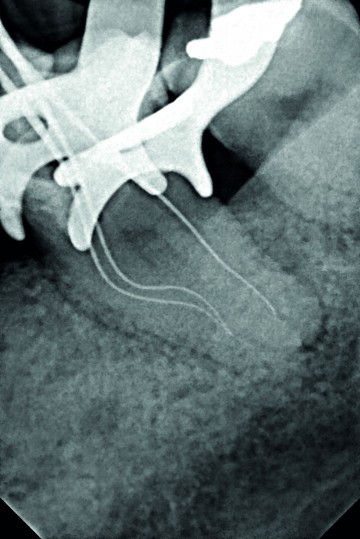

2/3 Peroperative x-ray Removal of the old restauration and the cavity. Working length (WL) determination.